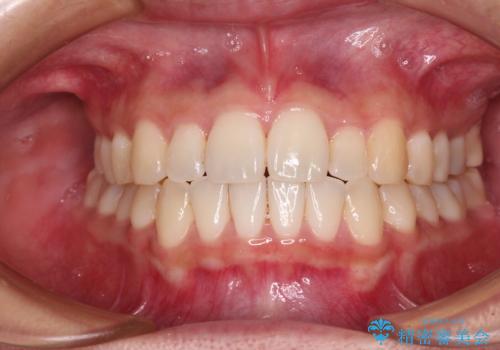

すきっ歯とオープンバイトをインビザラインで改善

- 前歯の上下スペースと前歯の隙間を気にして来院された患者様です。

インビザラインにより上下の前歯の隙間を閉じていくこととしました。

上下の隙間に舌が入り込むことが、すきっ歯やオープンバイトの原因であったため、舌の筋肉のトレーニングも並行して行い、後戻りの抑制を図りました。